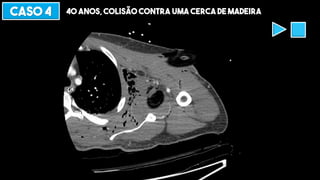

CASO 4 40 ANOS, COLISÃO CONTRA UMA CERCA DE MADEIRA

DIAFRAGMA, MEDIASTINO E AORTA